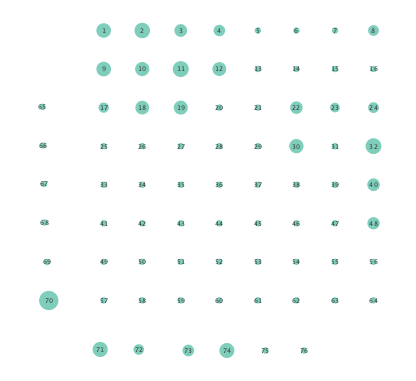

Figure 2 depicts networks inferred from different algorithms for both preictal and ictal intervals of the time series. The figure illustrates results obtained by the linear SVARM, and the K-SVARM approach with and without kernel selection. Each node in the network is representative of an electrode, and it is depicted as a circle, while the node arrangement is forced to remain consistent across the four visual representations. A cursory inspection of the visual maps reveals significant variations in connectivity patterns between ictal and preictal intervals for both models. Specifically, networks inferred via the K-SVARMs, reveal a global decrease in the number of links emanating from each node, while those inferred via the linear model depict increases and decreases in links connected to different nodes. Interestingly, the K-SVARM with kernel selection recovered most of the edges inferred by the linear and the K-SVARM using a polynomial kernel, which implies that both linear and nonlinear interactions may exist in brain networks. Clearly, one is unlikely to gain much insight only by visual inspection of the network topologies. To further analyze differences between inferred networks from both models, and to assess the potential benefits gained by adopting the novel scheme, several network topology metrics are computed and compared in the next subsection.

First, in- and out-degree was computed for nodes in each of the inferred networks. Note that the in-degree of a node counts its number of incoming edges, while the out-degree counts the number of out-going edges. The total degree per node sums the in- and out-degrees, and is indicative of how well-connected a given node is. Figure 3 depicts nodes in the network and their total degrees encoded by the radii of circles associated with the nodes. As expected from the previous subsection, Figures 3 (a) and (b) demonstrate that the linear SVARM yields both increases and deceases in the inferred node degree. On the other hand, the nonlinear SVARM leads to a more spatially consistent observation with most nodes exhibiting a smaller degree after the onset of a seizure (see Figures 3 (c) and (d)), which may imply that causal dependencies thin out between regions of the brain once a seizure starts.

Moreover, the performance of K-SVARM with data-driven kernel selection was also tested. Figure 7 illustrates the per node degree as well as the closeness centrality of networks inferred from preictal and ictal phases. Consistent with Figures 3 and 6, Figure 7 again reveals universal decrease in node degrees as well as closeness centrality at seizure onset.